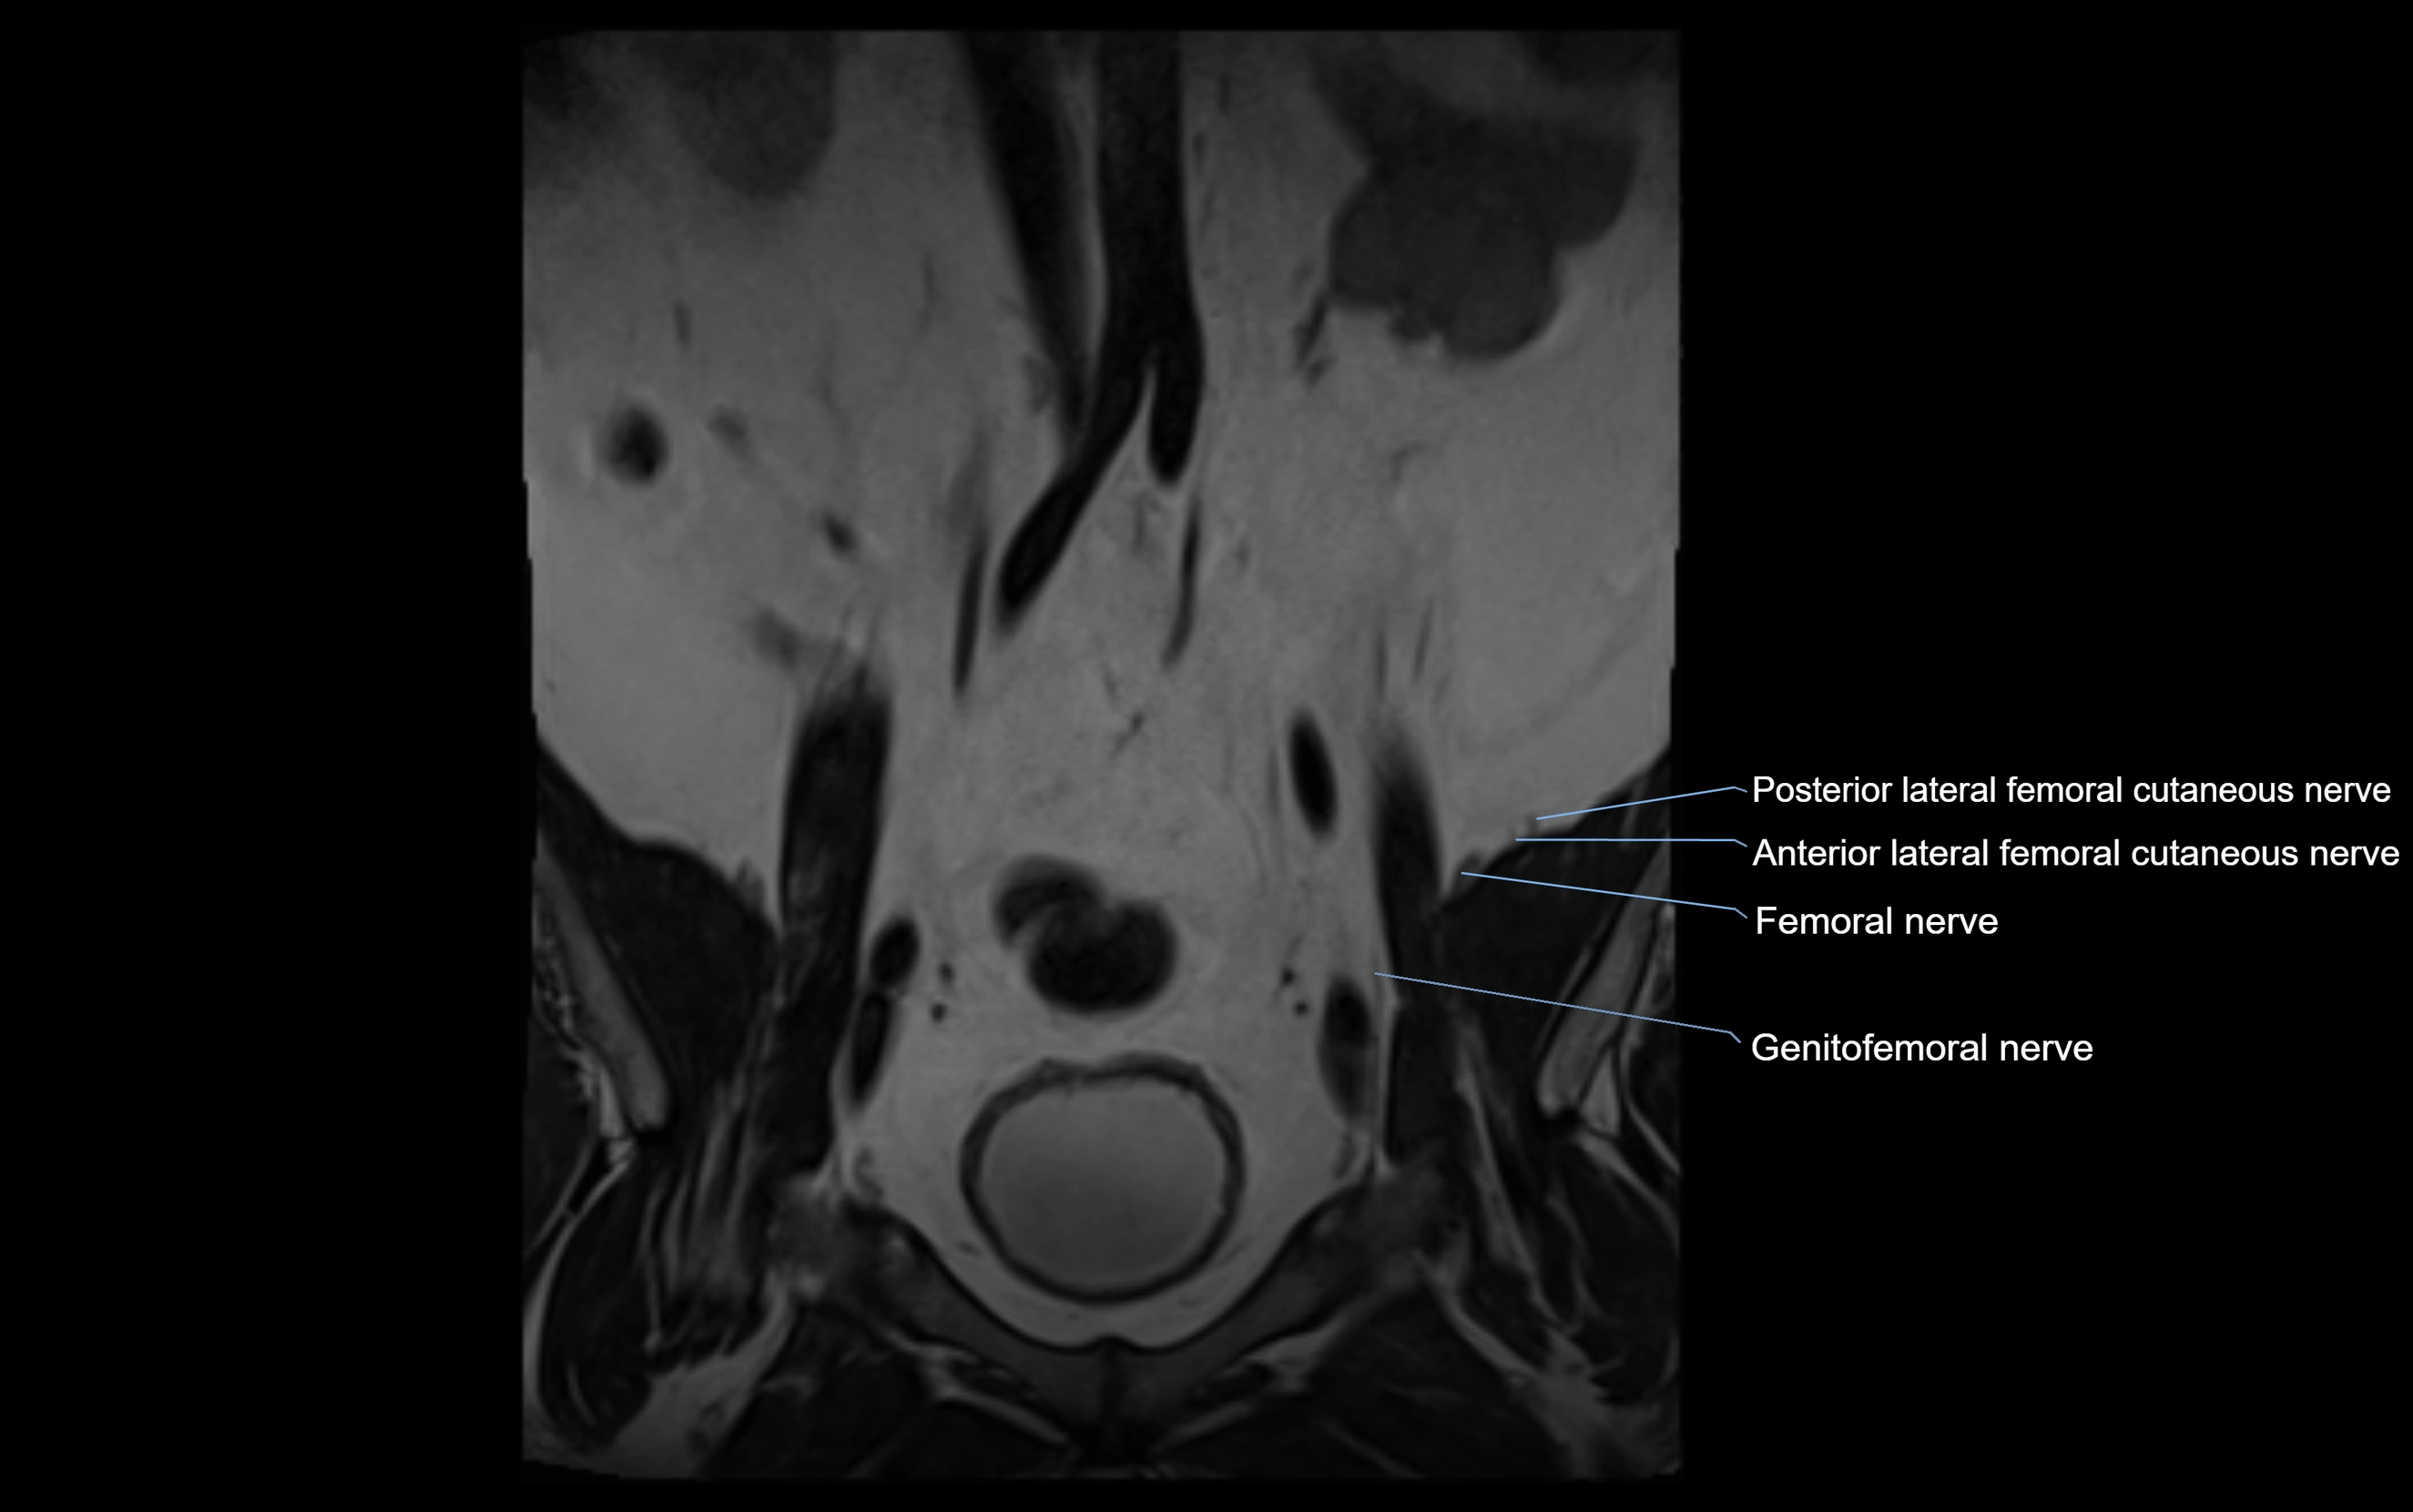

MRI Appearance

T1-weighted images:

• Nerve appears as a very thin low-to-intermediate signal intensity structure

• Surrounded by bright fat, aiding visualization

T2-weighted images:

• Nerve shows intermediate to mildly hyperintense signal compared to muscle

• Pathological involvement appears brighter

STIR (Short Tau Inversion Recovery):

• Normal nerve appears dark

• Inflamed or entrapped nerve appears bright hyperintense

T1 Fat-Sat Post-Contrast:

• Normal nerve enhances minimally

• Pathologic nerve (neuritis, entrapment, tumor infiltration) shows focal or diffuse enhancement

3D T2 SPACE / CISS:

• Nerve appears intermediate to mildly hyperintense compared to muscle

• Surrounded by bright fat or CSF, improving visualization

• Best sequence for mapping small pelvic nerves such as the anococcygeal